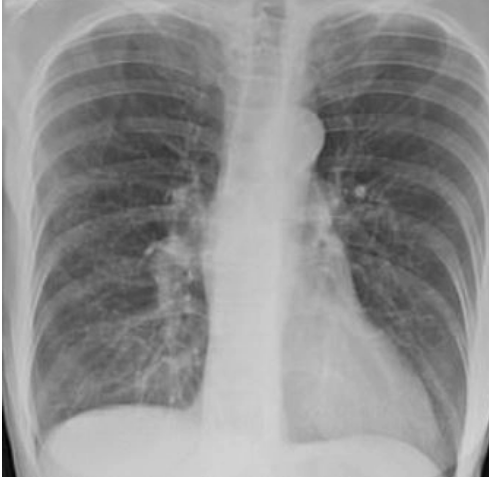

Одно изображение показывает нормальную здоровую пару легких, другое - легкие курильщика, а третье - легкие пациента с коронавирусом.

Нормальные легкие темные и прозрачные, на легких курильщика частично отмечены рубцами, в то время как легкие пациента с коронавирусом почти непрозрачны от повреждений.

picture Легкие курильщика